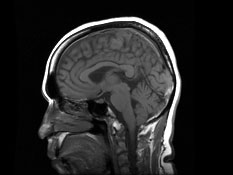

Magnetic resonance imaging (MRI) - The MRI machine uses magnets, radio waves and a computer to take very detailed pictures of the inside of your child’s body. Your child will have to stay very still for about 30 to 60 minutes during the MRI. Some children may receive anesthesia to help them stay still. Compared to older MRI machines, our 3T MRI machine and advanced processing protocols provide more-detailed images in less time.